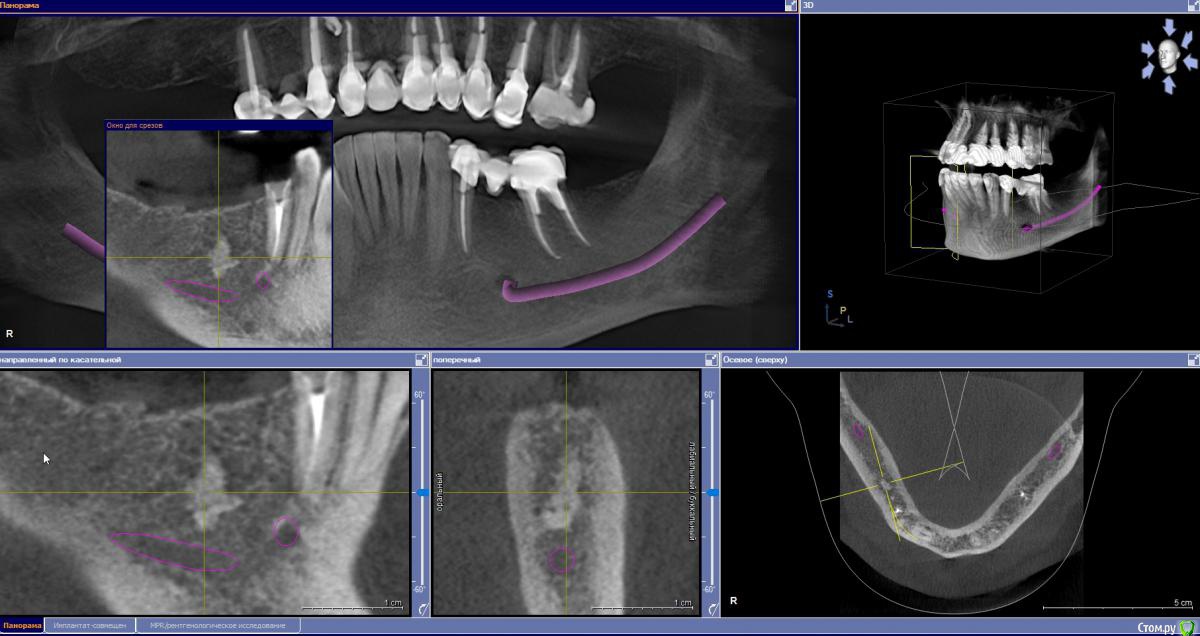

zumanok Опубликовано 21 мая, 2019 Поделиться Опубликовано 21 мая, 2019 Здравствуйте доктора.При планировании имплантации обнаружилось образование по плотности похоже на кортикальную кость, Обойти ее получается только при удалении соседнего корня и имплантации в 4.5- 4.7, хотя его можно восстановить. Как вы действуете в таких случаях или какое мнение? Есть ли подобный опыт? Ссылка на комментарий

krokomot Опубликовано 22 мая, 2019 Поделиться Опубликовано 22 мая, 2019 Это не одонтома, то что вы описываете больше походит на остеому или участок гиперостоза, и то и то не противопоказано при имплантации, в отличие от одонтомы. 2 Ссылка на комментарий